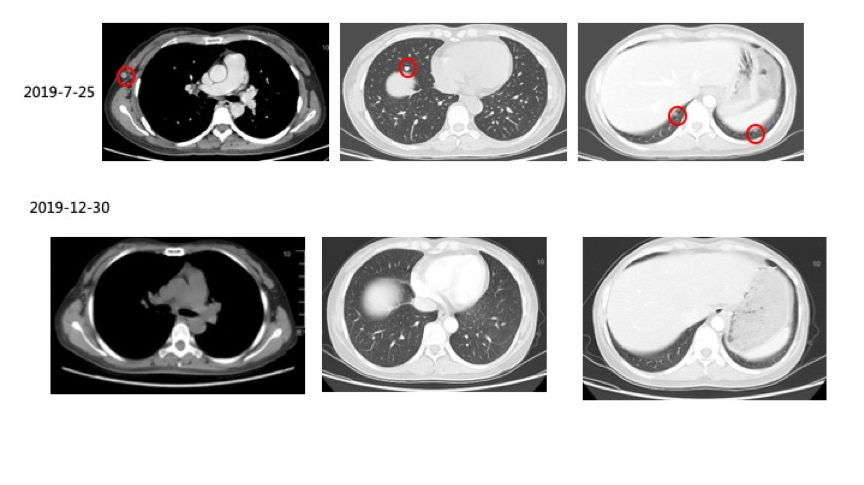

3)2019-07-25复查CT示:右侧腋窝皮下脂肪间隙新发结节,直径约8 mm,考虑转移瘤。双肺散在多发数个小结节,较大约直径约7 mm,较前新发,考虑转移瘤可能性大。患者出现新病灶,疗效评价为PD。联合治疗阶段累积免疫帕博利珠单抗治疗8周期、维莫非尼8个月。

(图2:维莫非尼停药2个月后复查CT显示,右侧腋窝皮下脂肪间隙新发结节、双肺散在多发转移瘤,疗效评估PD)

2)2019-09-26复查CT:右侧腋窝皮下脂肪间隙结节,考虑转移瘤,较前缩小。原双肺散在小结节,较前缩小,现已不明显。

3)2019-12-30复查CT:右侧腋窝皮下脂肪间隙结节较前继续缩小;双肺结节消失。